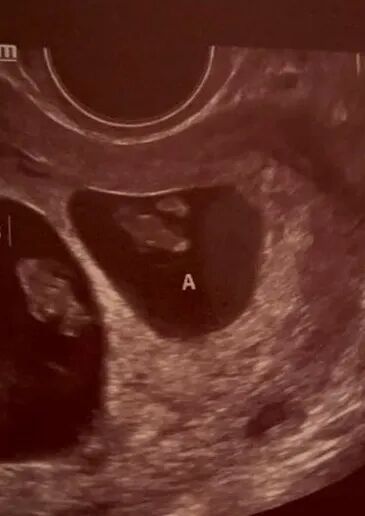

还记得那位来自加州的甜美可爱的爱妈J吗?她前不久验孕成功,今天在诊所进行了首次体检,并激动地听到了宝宝的心跳声!虽然她与来自上海的准妈妈相隔千里,但这份激动和期待的心情已经跨越了地理的界限。宝宝的每一次检查,两地的妈妈们都充满了期待和喜悦,共同期盼着下一次美好的消息。